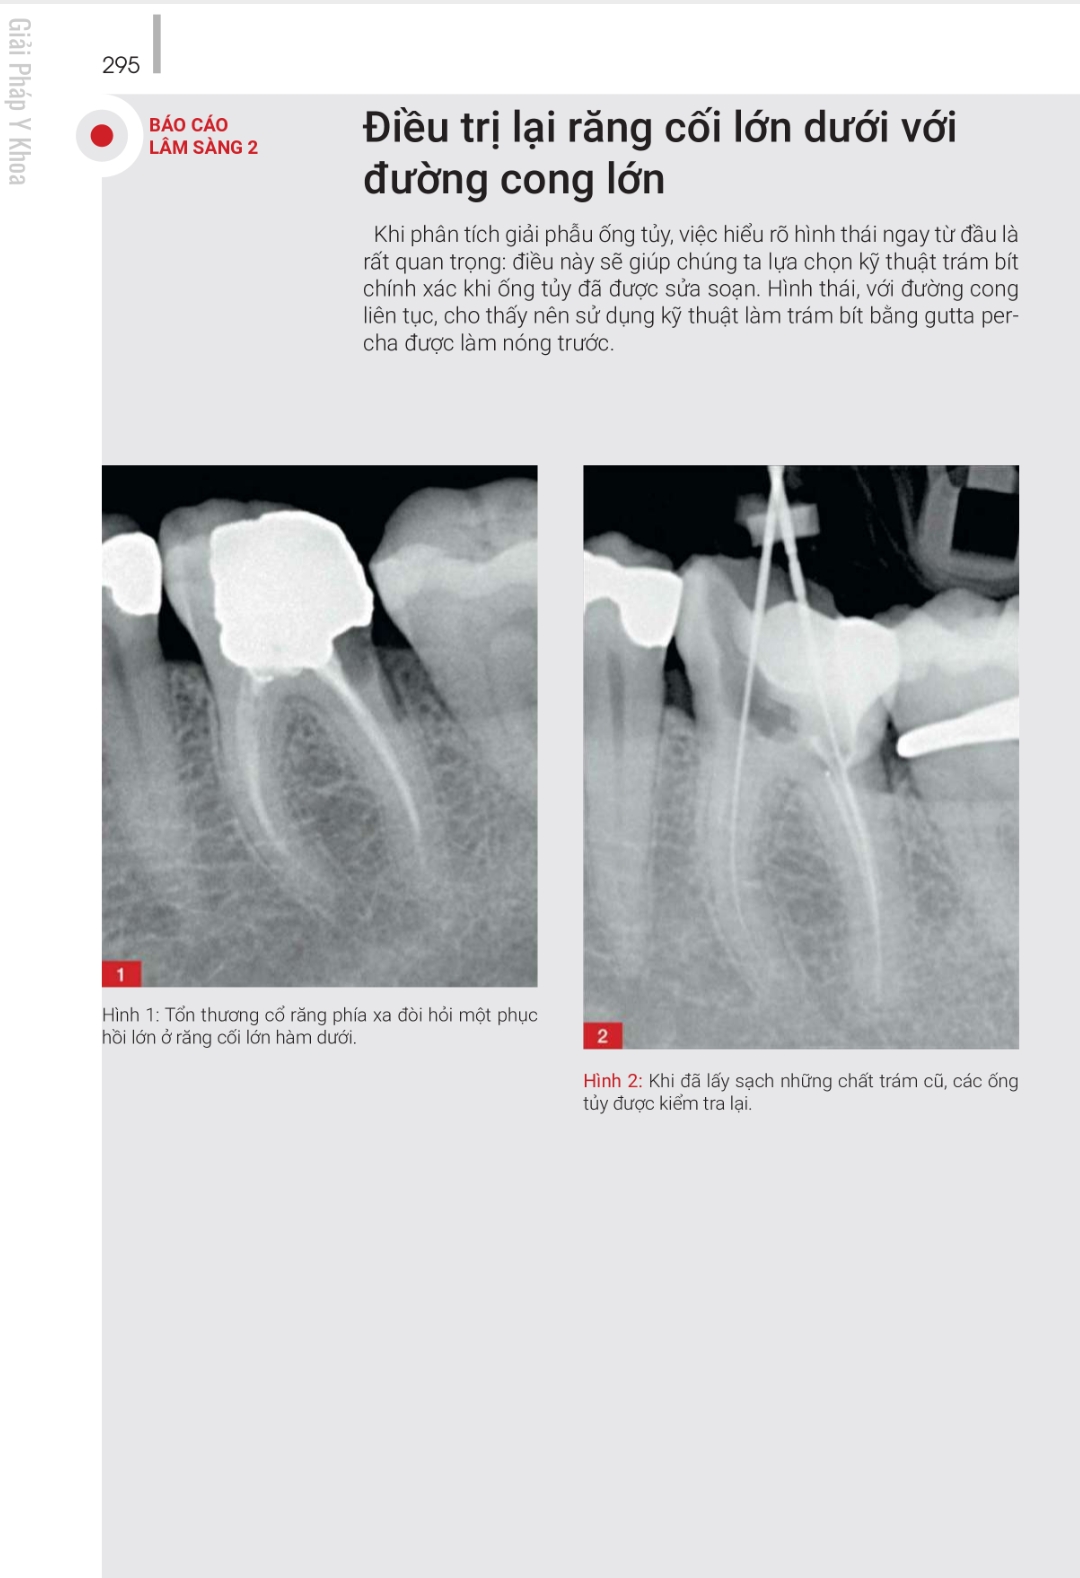

ĐIỀU TRỊ LẠI – NHỮNG GIẢI PHÁP SANG THƯƠNG QUANH CHÓP NGUỒN GỐC TỪ NỘI NHA